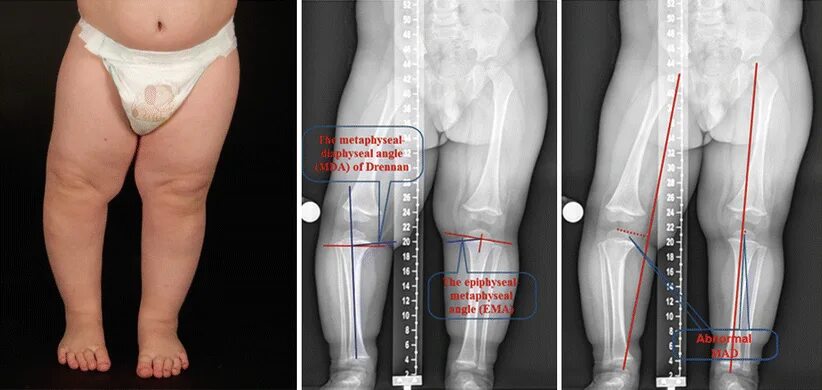

Укорочение трубчатых